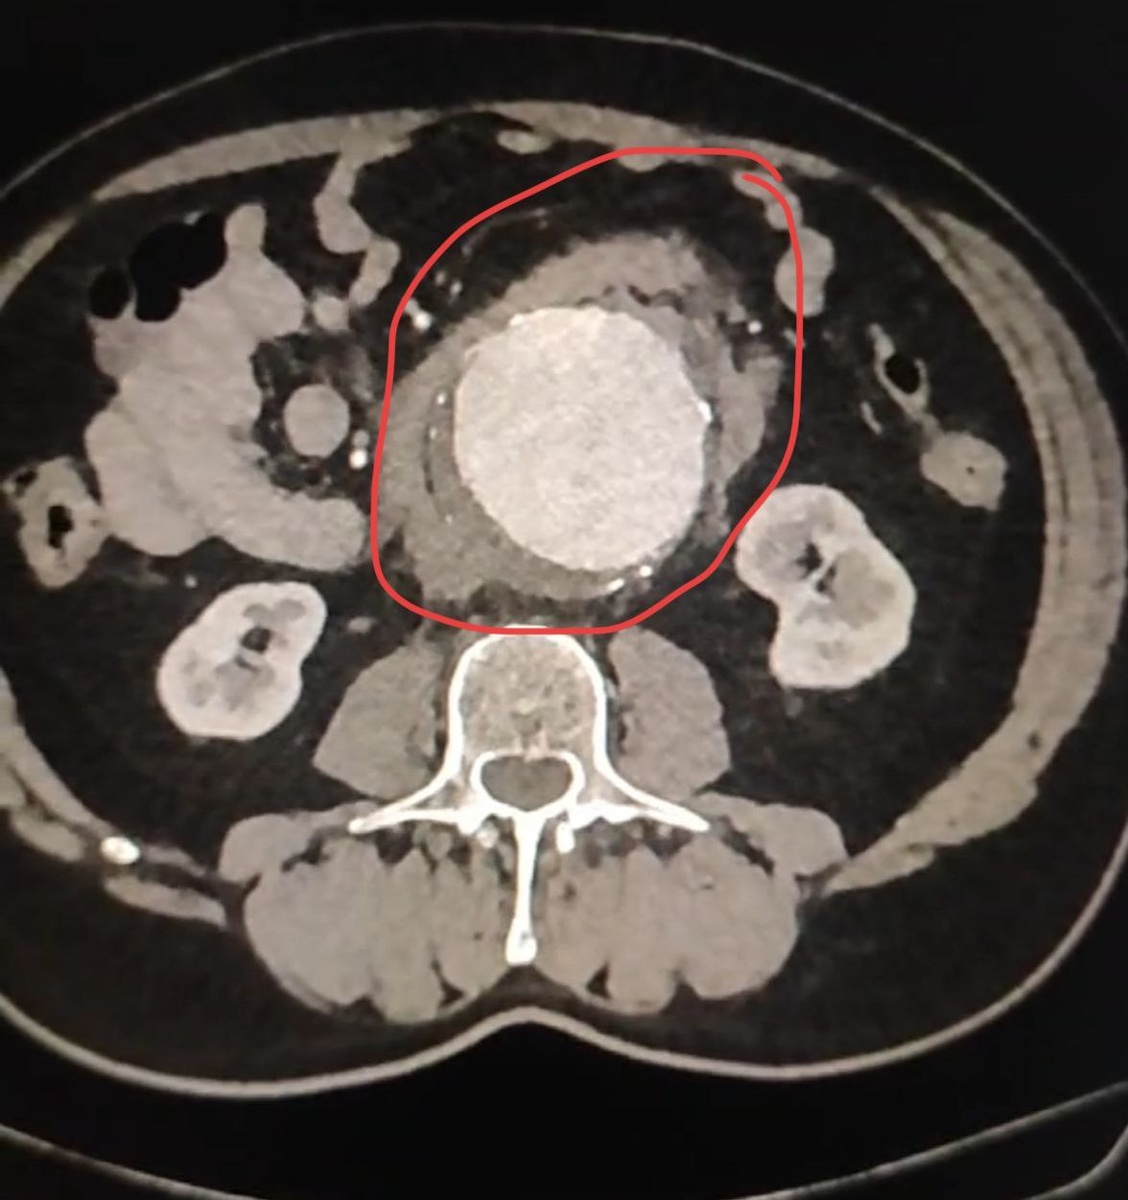

🚨В больницу округа был доставлен 66-летний пациент с подозрением на разрыв аневризмы брюшной аорты.

Как пояснили в Долгопрудненской больнице, аневризма брюшной аорты - опасное заболевание, при котором сосуд расширяется. Аорта приобретает форму шара с истончёнными стенками, и возникает угроза её разрыва.

❗️У больного разрыв аневризмы всё-таки произошёл, часть крови излилась в забрюшинное пространство. Летальность при данном состоянии без операции составляет 100%.

Наши врачи под руководством заведующего отделением сосудистой хирургии Алексея Варина провели экстренную операцию. Они успешно выполнили протезирование брюшной аорты: заменили поражённый участок на синтетический сосудистый протез.